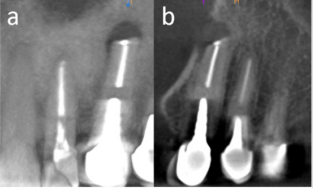

Cone-Beam Computer Tomography (CBCT) showed a round periapical radiolucency at the apex of tooth 2.3 and the resorption of the afferent buccal bone (Figure 3). Ultrasound investigation was performed using a EUP-O54J hockey stick linear transducer with a 25 mm width scan (frequency 7-13 MHz, Hitachi Noblus, Arrieta). Ultrasound imaging (Figure 4) showed a 6/1.5 mm diameter hypoechogenic structure at the apex of tooth 2.3, with a more intense hypoechogenic extension to the medial and superior maxillary vestibule. Intraoral EcoDoppler ultrasonography (Figure 5) revealed the avascular characteristics of the apical fibrous mass and the blood flow present only on the peripheral area of the fibromatous appearance. Giving the clinical features and ultrasonography investigation, the diagnosis of vestibular fibroma was set. In local anesthesia (Articain 1/100000), the detachment and excision of the fibrous structure from the vestibular mucosa were performed (Figure 6). Due to the structure’s adherences, the periosteum was also removed (Figure7). Curettage of the previous surgery situs and flap suture were carried out (Figure 8). The harvested specimen was sent for histopathological examination and revealed the presence of connective tissue with extensive areas of hyalinization and minimal lymphocytic inflammatory infiltrate (scarring changes).

Figure 3: CBCT examination. Coronal (a) and sagittal (b) sections evidence buccal cortical resorption at periapical level of upper left canine and the extension of the resorbtive process along the mesial side of the tooth.